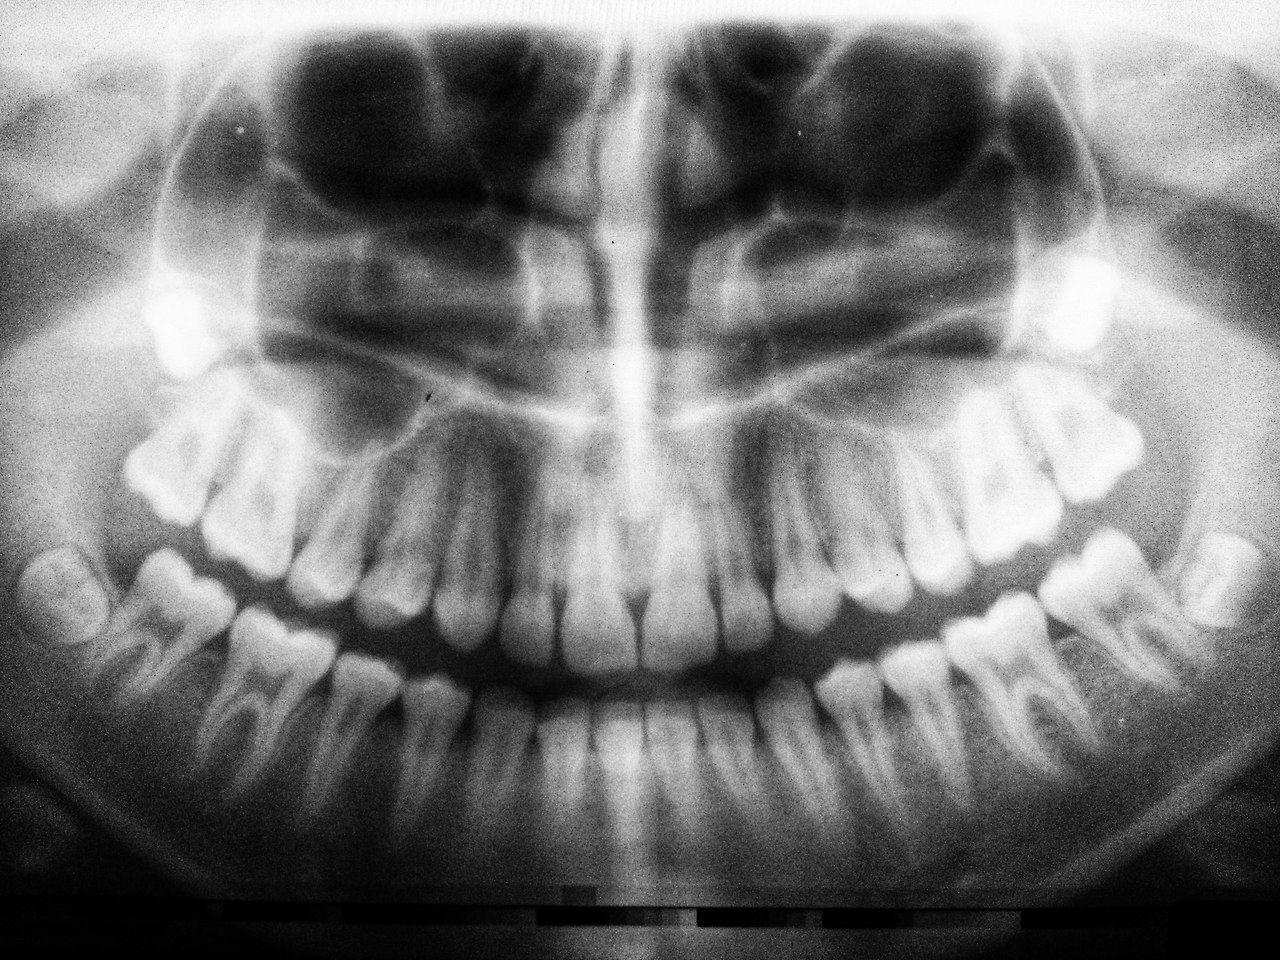

노가리가 너무 질기고 단단했던 모양이다. 뭔가 이상하다 싶었는데 윗 치아 하나에서 작은 조각이 떨어져 나갔다. 꺼끌한 느낌도 그렇고 걱정도 돼서 목구멍 가까운 안쪽이라 어두운데도 폰으로 찍었다. 확대해 보니 둥근 피자에서 1/8 조각을 떼어 낸 형태로 떨어져 나갔다.

피가 난 것도 통증도 없으니 주말을 보내고 치과를 찾으면 될 일인데 자꾸 신경이 쓰여 그 치아를 혀로 더듬고 연방 사진과 비교하다 깨달았다. 눈보다 혀가 더 예민하고 정확하다는 것을...

사진으로는 보이지 않는 작은 틈새를 혀가 그려내고 있었던 것이다. 사물을 볼 때 눈으로 보는 것이 1이고 뇌가 9를 담당하니 실은 뇌가 보는 게 맞다. 혀가 그 미묘한 차이 가령 날카롭고, 파인 구석까지 그 굴곡을 너무도 선명하게 연상시켜 주는 게 신선한 충격이다.

치아는 탈이 나기 전까지 그 은밀하고도 중요한 역할을 드러내지 않는다. 응당 입으로 들어온 것이면 반사적으로 저작을 하는 정도로만 여기기 마련이다. 음식을 제대로 씹지 못한다면 건강을 해치고 최악의 경우에는 생명까지 위협한다.

작은 조각 하나가 떨어져 나갔을 뿐인데 은연 중에 혀로 더듬고 있다. 떨어져 나간 부위가 껄끄럽기도하고 패인 구멍에 자꾸 혀끝을 밀어넣고 살피게 된다.

틀니를 하고 있었거나 임플란트를 경험한 사람은 안다. 빠진 이 하나 때문에 양쪽 치아가 기울고 흔들린다. 그렇게 하나가 세 개가 되고 다섯개가 되다보면 마침내 수습할 수 없는 국면을 맞이한다.